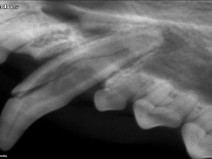

• Module 5 : Plan modulaire de formation en dentisterie

La stomatologie est une discipline survolée lors des études vétérinaires et pourtant elle occupe une place importante au sein de l’activité de l’omnipraticien . Ce cours modulaire permet d’acquérir des bases théoriques solides en dentisterie et stomatologie tout en assurant une formation pratique de qualité. Les participants devront être capables à leur issue d’adopter au sein de leurs établiss...

En savoir plus

b80038f6fcf727e035d3ed80dcef46b6

Du 10 au 12 octobre 2016

NANTES (44300)

Dentisterie-Stomatologie

G.E.R.O.S.

116